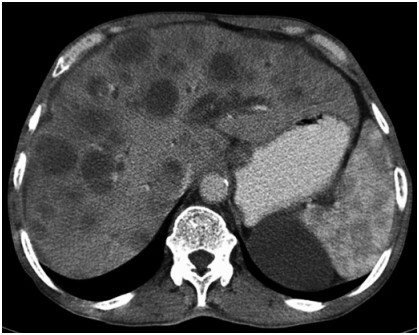

Abstract: Hepatic EHE (epithelioid hemangioendothelioma) is an uncommon entity of vascular origin and a low-grade malignant tumor. Primary hepatic EHE is rare. These tumors can be multifocal at presentation like in the soft tissues, bones, brain, liver, and small intestine. First described by Weiss and Enzinger in 1982 as a malignant vascular neoplasm with indolent behavior. We report the case of a 23-year-old male, known case of chronic liver disease, who presented with incisional hernia following exploratory laparotomy 8 months back, performed for intestinal obstruction. Contrast-enhanced computed tomography abdomen revealed an incisional hernia with a large defect along with multiple lesions in the liver (suspected metastases) and peritoneal deposits and a few discrete lung nodules. Some areas of interloop collections were also noted. Biopsies were taken from the liver which revealed benign cirrhotic lesion. Relevant to the findings, multiple biopsies were performed and fluid was sent for evaluation. The liver biopsy came out positive for borderline vascular malignancy (epithelioid hemangioendothelioma). This was confirmed with the immunohistochemistry report. Epithelioid hemangioendothelioma occurs mostly in soft tissues of extremity and lungs. The involvement of the liver may be seen as metastasis or rarely as a primary tumor. The incidence of primary malignant hepatic hemangioendothelioma is about 0.1/100,000; the mean age at the time of diagnosis is 41.7 years, and male:female ratio is 2:3. Liver transplantation, hepatectomy, chemoembolization, radiotherapy, and chemotherapeutic agents are reported treatment regimens. Malignant EHE of liver presents as multiple hepatic nodules. Being locally aggressive, it can invade the peritoneum, gut, and lungs. Orthoptic liver transplantation appears to be the only remedy because of the multifocal nature of the disease. Partial hepatectomy is possible for localized tumors.